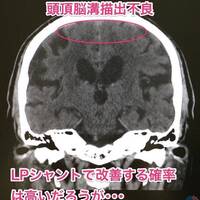

髄液排除試験(タップテスト)で歩行が改善しても、本人が納得しなければ手術は出来ない。(当たり前)

検査や治療を行うに当たっては、当然だが本人の同意が必要である。しかし、患者さんが認知症の場合、本人の同意を得るのは途端に難しくなる。 ただし、認知症により理解力や判断力が落ちていても、本人が穏やかに医者の説明を聞くことができて、かつご家族のご理解と同意があれば、それを「ご本人、ご家族の同意」として検査や治療を行…